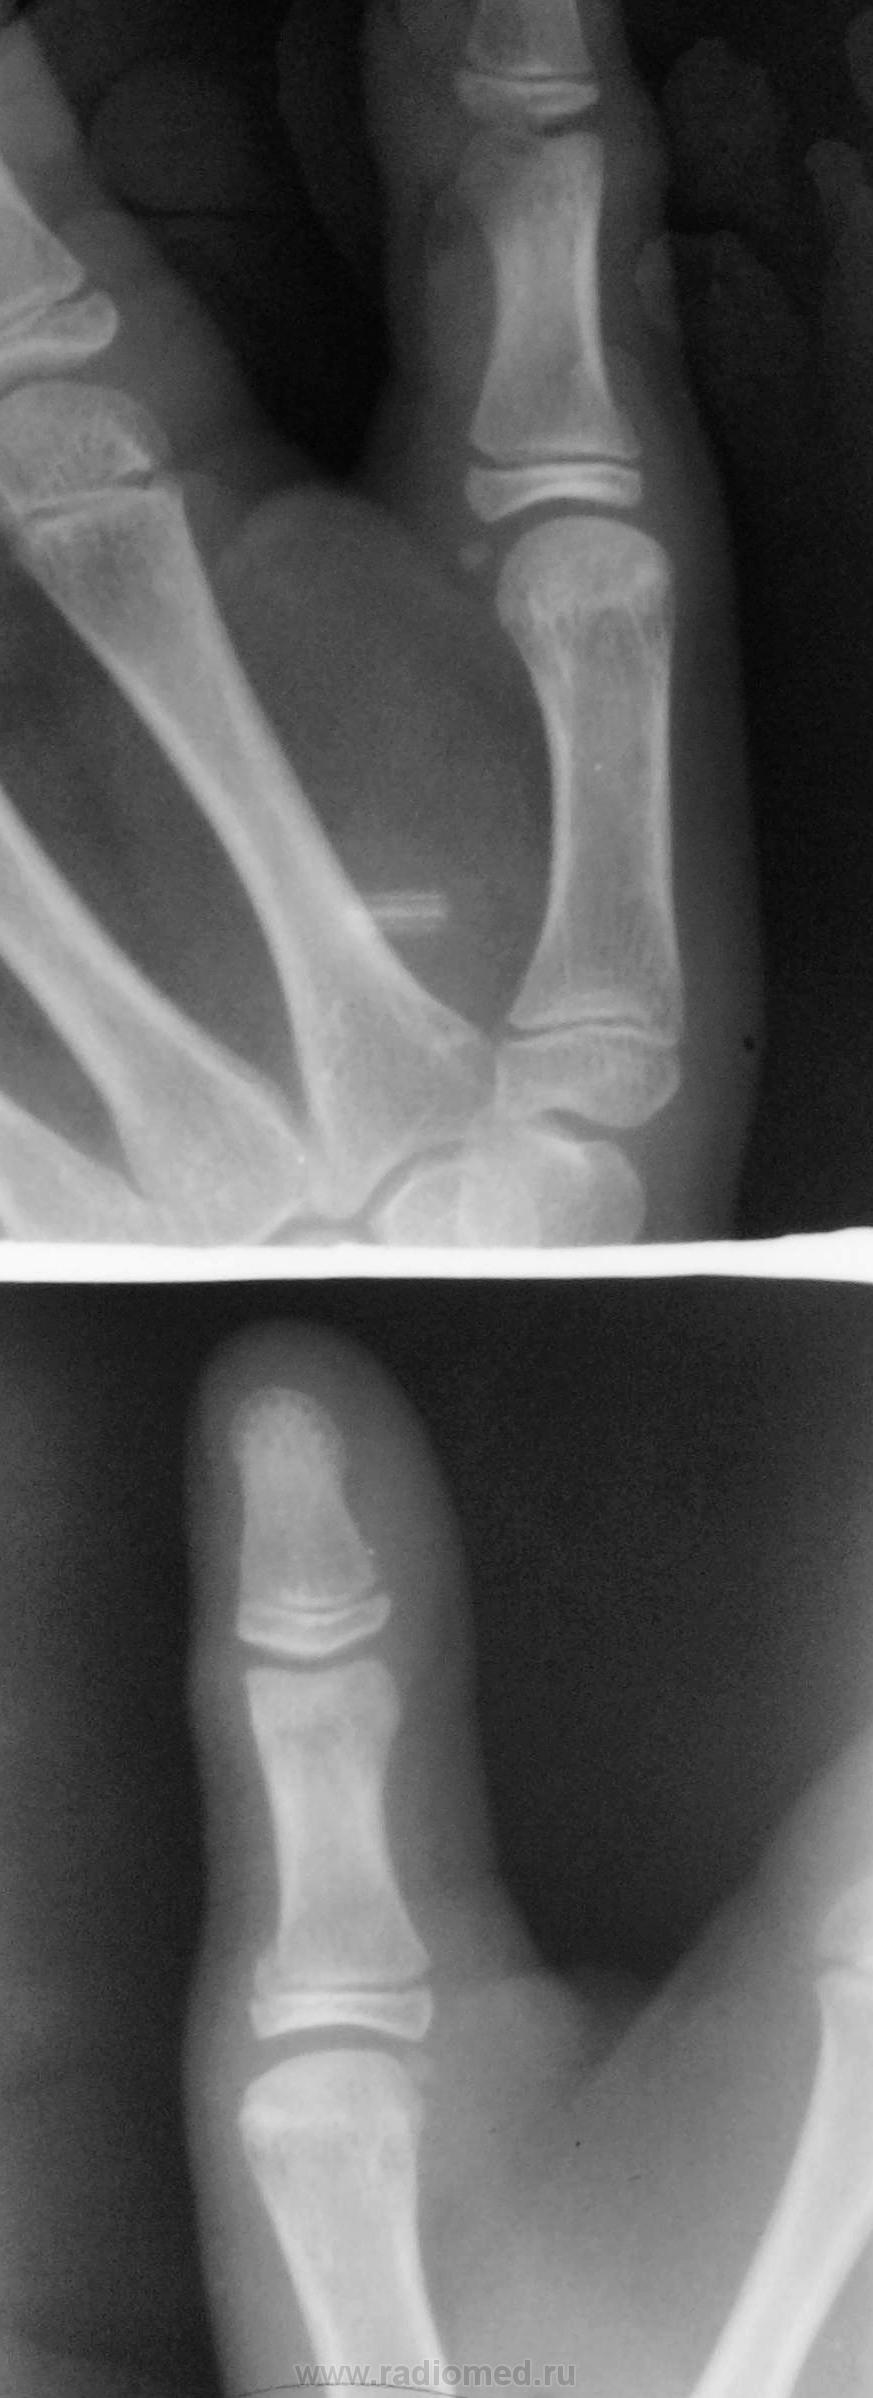

Рентгенография 1-го пальца. Девочка 11 лет.Травма.

Остеоэпифизеолиз о/ф первого пальца.

А что смущает? вроде обычный остеоэпифезиолиз проксимального эпифиза дистальной фаланги 1пальца   кисти.